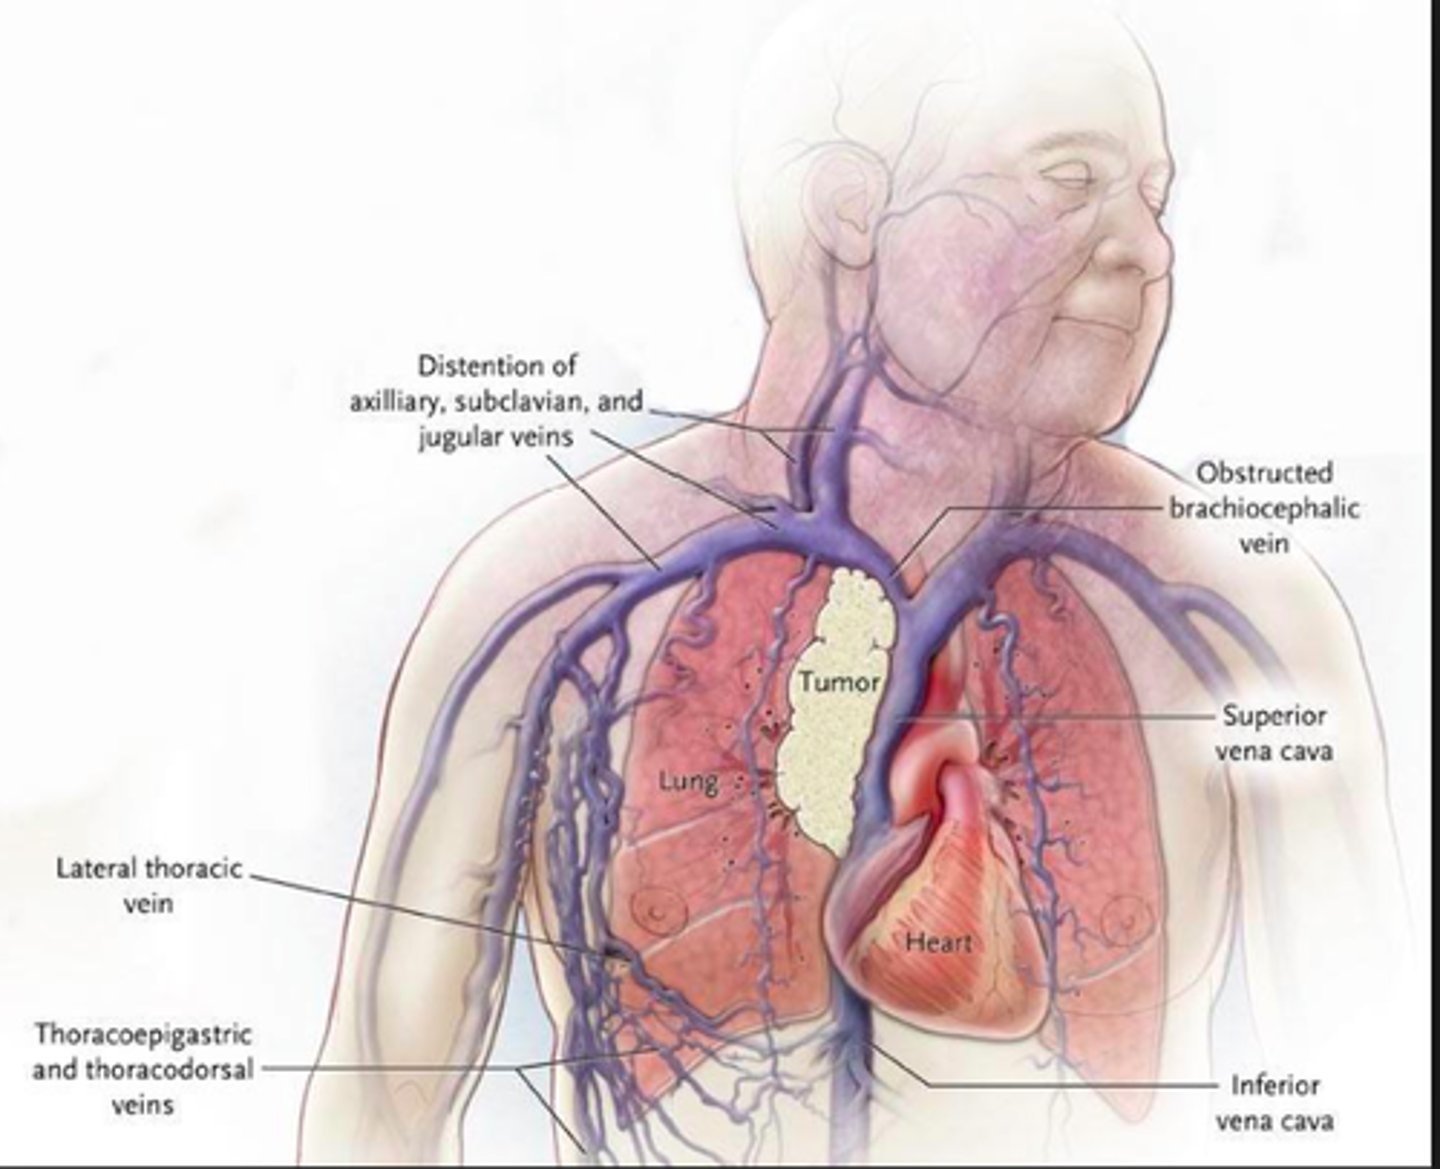

Dyspnea

Venous congestion

Swelling of the head, neck, and arms

Hx smoking

Superior vena cava (SVC) syndrome

- malignancy most common cause obstruction (lung cancer small cell, nonHodgkin lymphoma)

- x-ray chest, followup with chest CT and histo